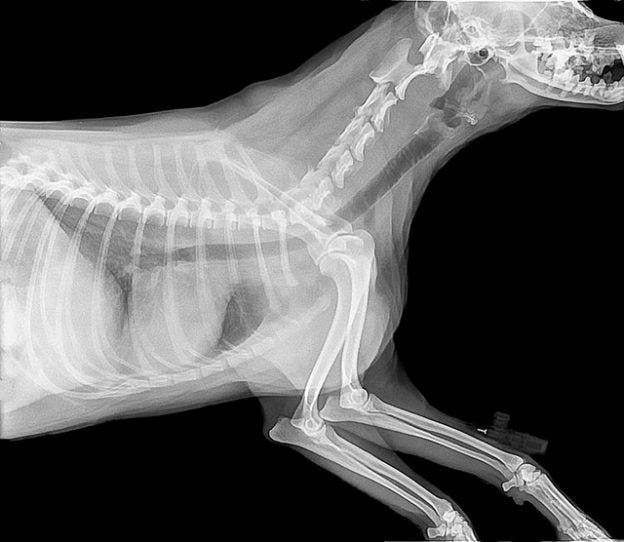

This course is intended for veterinarians who are interested in building a solid foundation interpreting non-cardiopulmonary abnormalities in thoracic radiographs of dogs and cats. The course will cover anatomy of the thorax, trachea, esophagus, mediastinal structures, pleural space, ribs and sternum. By the end of the course the participant should understand the normal anatomy of the thorax, be able to recognize abnormalities in the trachea, esophagus, mediastinum, pleural space, ribs and sternum.

This session will cover the normal anatomy of the thorax in dogs and cats and discussion on how to compare normal radiographs.

Week 2 (Real Time Session May 17, 2021): Trachea and Esophagus

Week 3 (Real Time Session May 24, 2021): Mediastinal Structures

Week 4 (Real Time Session June 7, 2021): Pleural Space

Week 5 (Real Time Session June 10, 2021): Ribs and Sternum